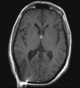

Colloid cyst of third ventricle

A colloid cyst is a non-cancerous tumor in the brain. It consists of a gelatinous material contained within a membrane of epithelial tissue. [Source: Wikipedia ]